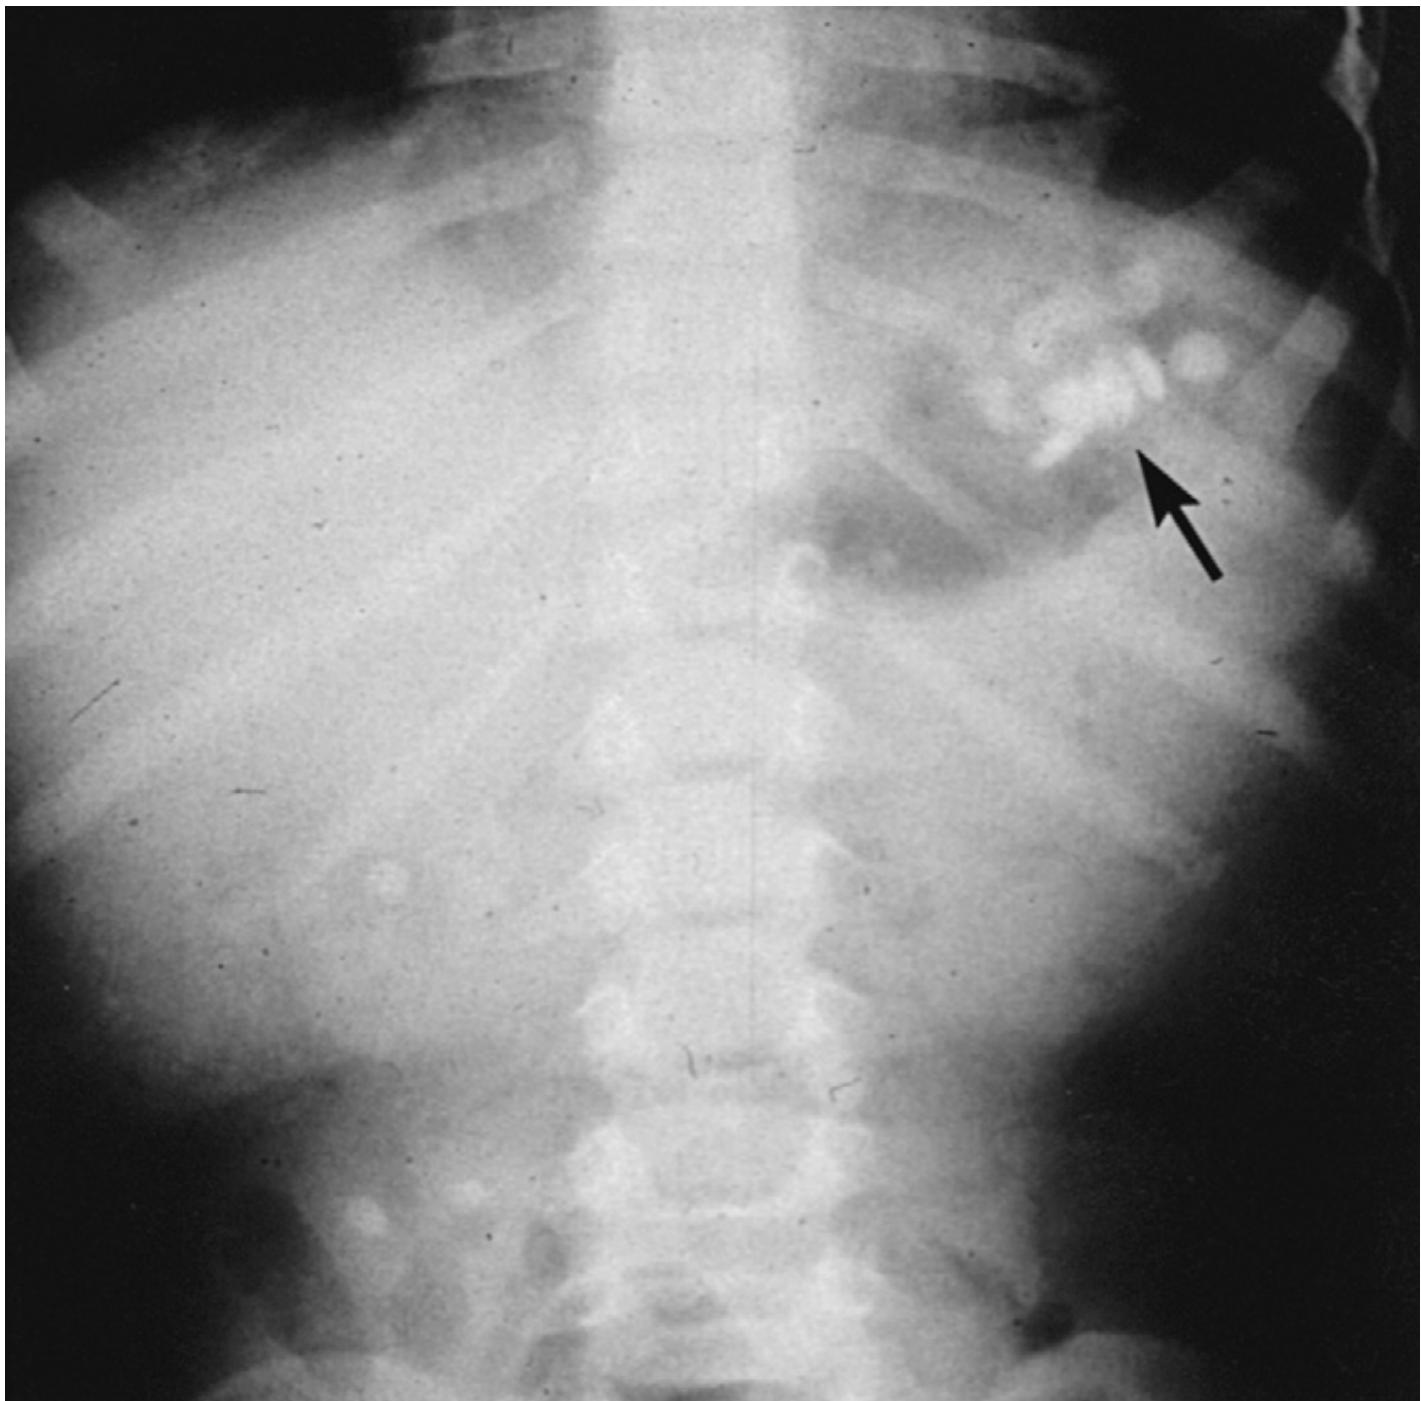

- Significant number of pills visible on abdominal radiography